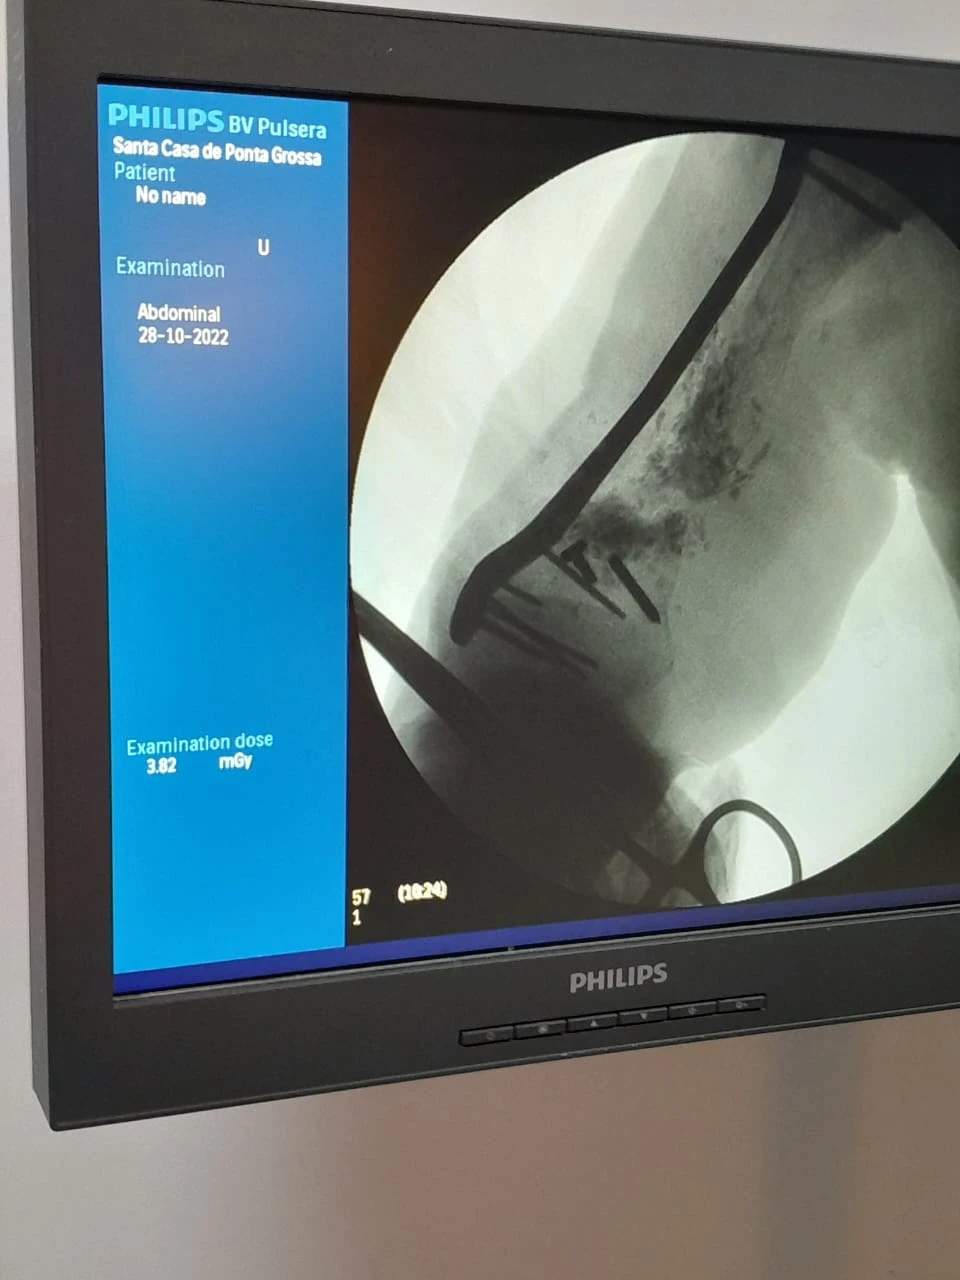

No último dia 28, a equipe de Ortopedia e Traumatologia da Santa Casa de Ponta Grossa realizou um procedimento cirúrgico inédito na região dos Campos Gerais, que consiste na correção de ossos em situações de fraturas. Neste caso, a paciente em questão fraturou o úmero (osso superior do braço), passou por diversas cirurgias em outras instituições, porém sem obter sucesso. O cirurgião Dr Carlos Miers explica a dificuldade para a realização do procedimento: “a cada cirurgia realizada a quantidade de osso disponível no braço era menor, e quando a paciente chegou até mim ela já tinha o úmero direito muito menor que o esquerdo, e com um defeito ósseo grande." A primeira etapa do tratamento consistiu em tratar a infecção, após isso foi necessário fazer um transporte ósseo com fixador externo, utilizado pela paciente durante 2 anos. Em seguida foi necessário estabilizar e fixar o úmero da parte superior até a inferior, porém não havia placa/haste disponível no mercado que supria a necessidade desta paciente “aí que começa a singularidade deste procedimento, nós em parceria com a empresa Neoortho, desenhamos e desenvolvemos uma placa personalizada especifica para a anatomia desta paciente”, explica o profissional. O projeto de personalização da placa foi realizado utilizando tecnologia de ponta através e modelos computacionais extraídos de tomografia, simulações mecânicas em elementos finitos para garantir que o material não iria falhar durante o tratamento: “após diversos testes chegou-se a versão final da placa que foi instalada na paciente durante a cirurgia”, complementa o Dr Carlos. Participaram da cirurgia os profissionais Dr Carlos Miers e o Dr Rodrigo Favaro, o procedimento foi realizado no centro cirúrgico da Santa Casa, durou 4 horas e foi um sucesso. A Instituição que é referência para 28 municípios vem traçando estratégias para cumprir sua missão de acolher e tratar o paciente respeitando sua individualidade, proporcionando uma experiência em saúde com ética, segurança, tecnologia e resolutividade. [gallery size="medium" ids="137648,137649,137650"]